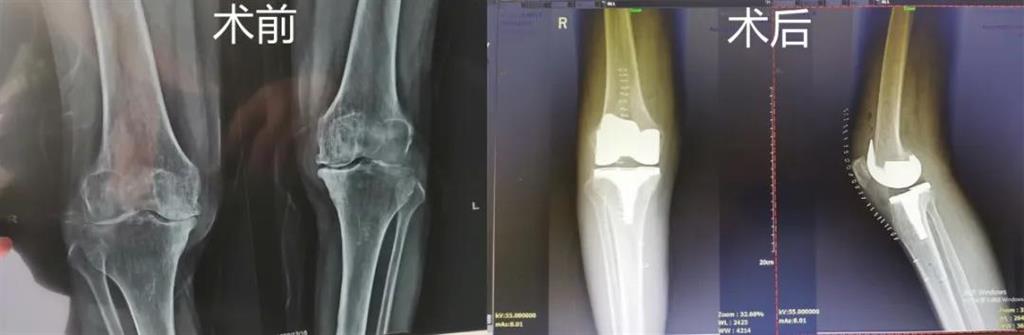

計(jì)算機(jī)導(dǎo)航膝關(guān)節(jié)置換術(shù)過(guò)程部分畫(huà)面